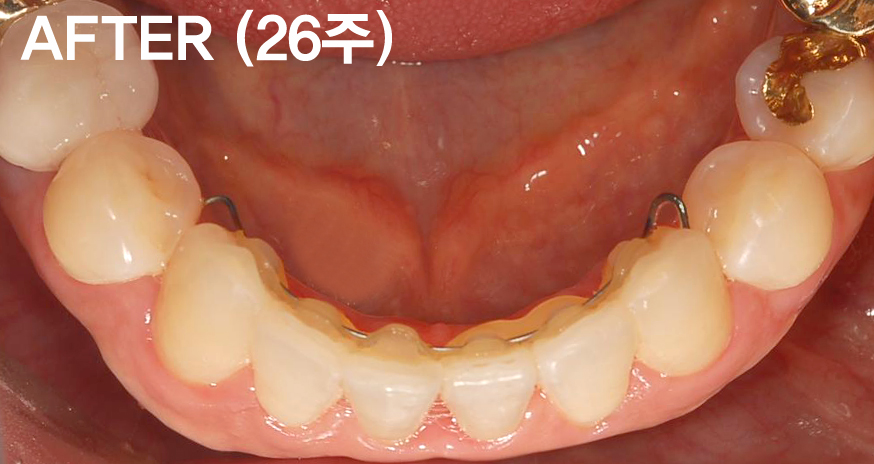

궁금한 내용은 아랫 앞니부분이 부분교정이 가능한지 궁금하신것 같습니다.

앞니가 삐뚤하기 때문에 치아표면에 착색이 되어 충치처럼 보입니다.(착색이지 충치는 아닙니다. 치아를 교정하면 치솔질이 용이하기때문에 착색이 생기는것도

교정기간은 5개월전후면 충분히 가능하고 비용은 150만원(월교정비는 4만원)입니다.